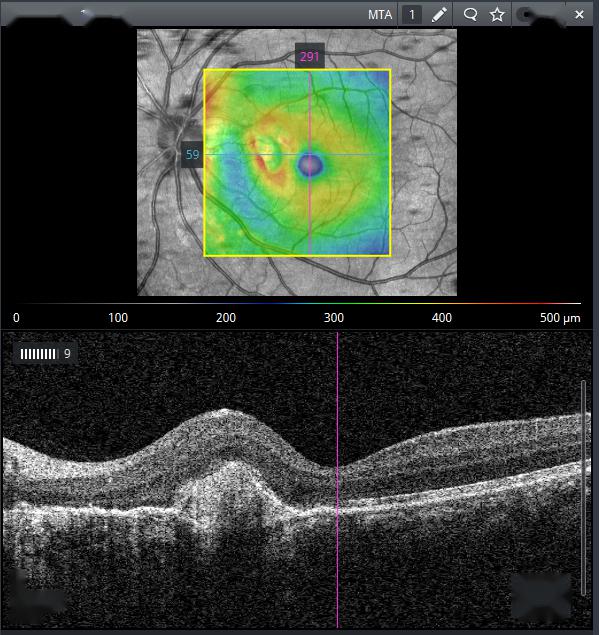

高度近视脉络膜新生血管光相干断层扫描血管成像特征及黄斑区脉络膜